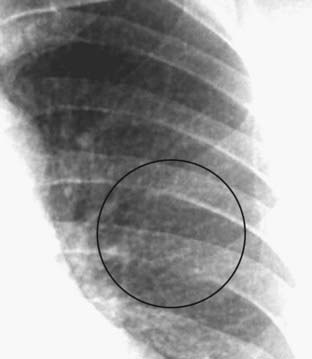

Figure 7-9 Miliary tuberculosis.

Innumerable small round nodules are present in this close-up of the left lung in a patient with miliary tuberculosis (black circle). At the start of the disease, the nodules are so small they are frequently difficult to detect on conventional radiographs. When they reach about 1 mm or more in size, they begin to become visible. Miliary tuberculosis will clear relatively rapidly with appropriate treatment and does not heal with calcification.